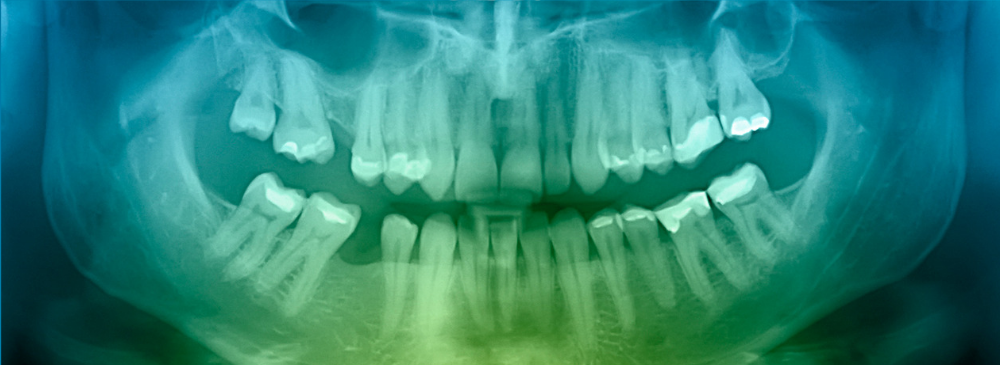

Why We Don’t Always Notice the Color of Our Cavities

All of this information about the color of cavities is useful, but truth be told, many cavities are hidden and hard to spot. Most cavities form in difficult-to-reach places, like between the teeth or near the gum line. Often, you won’t notice a cavity until your dentist detects it with an x-ray or dental exam. Understanding the color of your cavities is important, but visiting the dentist is always your best line of defense.